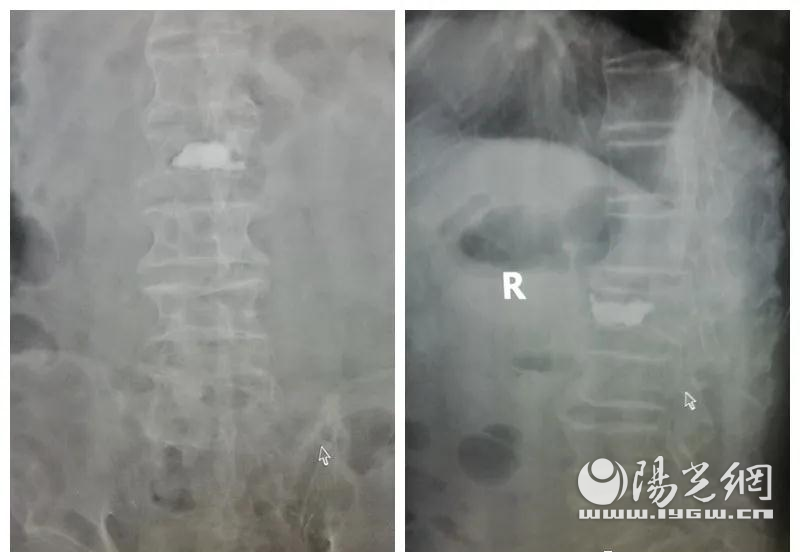

鼠年伊始,一场疫情笼罩大地,全国上下团结一心,众志成城,对于普通老百姓来说,自觉封闭在家就是对祖国最大的贡献。家住西安市的乐老先生,一个月前在家不慎摔了一跤,腰背部疼痛厉害,为了响应国家疫情期间不外出的号召,乐老先生忍痛坚守在家一个月。随着复工复产开始,乐老先生带着“一码通”慕名来到西安市中心医院郭华副院长专家门诊看病,通过影像检查后,确诊了腰椎Kummell病,随即住院治疗。

入院后姬钢主任医师、郭健主治医师为乐老先生进一步做好术前准备,3月12日郭院长为患者行PKP微创手术,手术效果满意,疼痛明显减轻,手术当日就可以下地行走了。

据郭华副院长介绍,Kummell病又称陈旧性椎体骨折骨不连,多是因为椎体发生了骨折,但没有及时的得到规范的治疗,导致最终骨折不愈合甚至缺血坏死,乐老先生正值新冠肺炎期间在家中摔倒,未及时就医,导致了骨折加重,精神可贵做法却不妥。目前西安市中心医院也在不断有序的恢复,郭华副院长提醒大家,如果感觉身体出现问题需及时就医,以免延误病情。